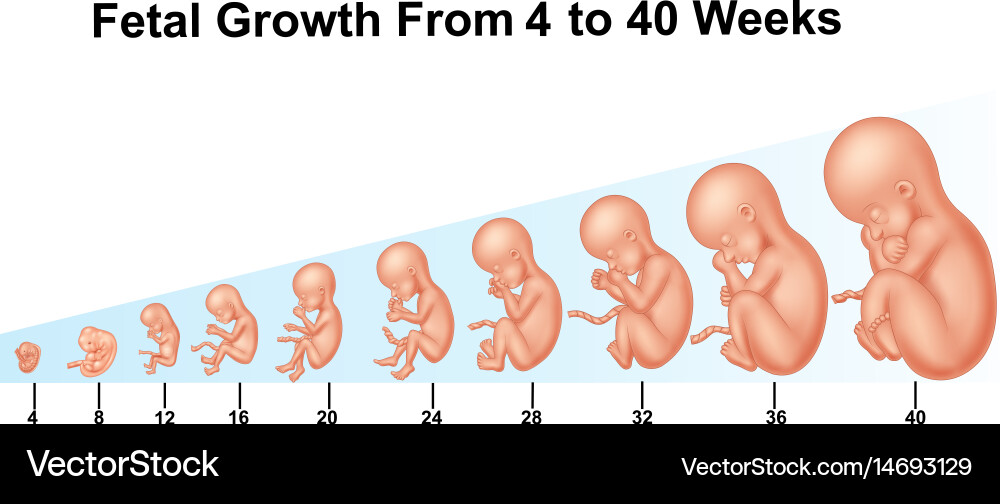

Формирование Плода в Первом Триместре: Важные Этапы